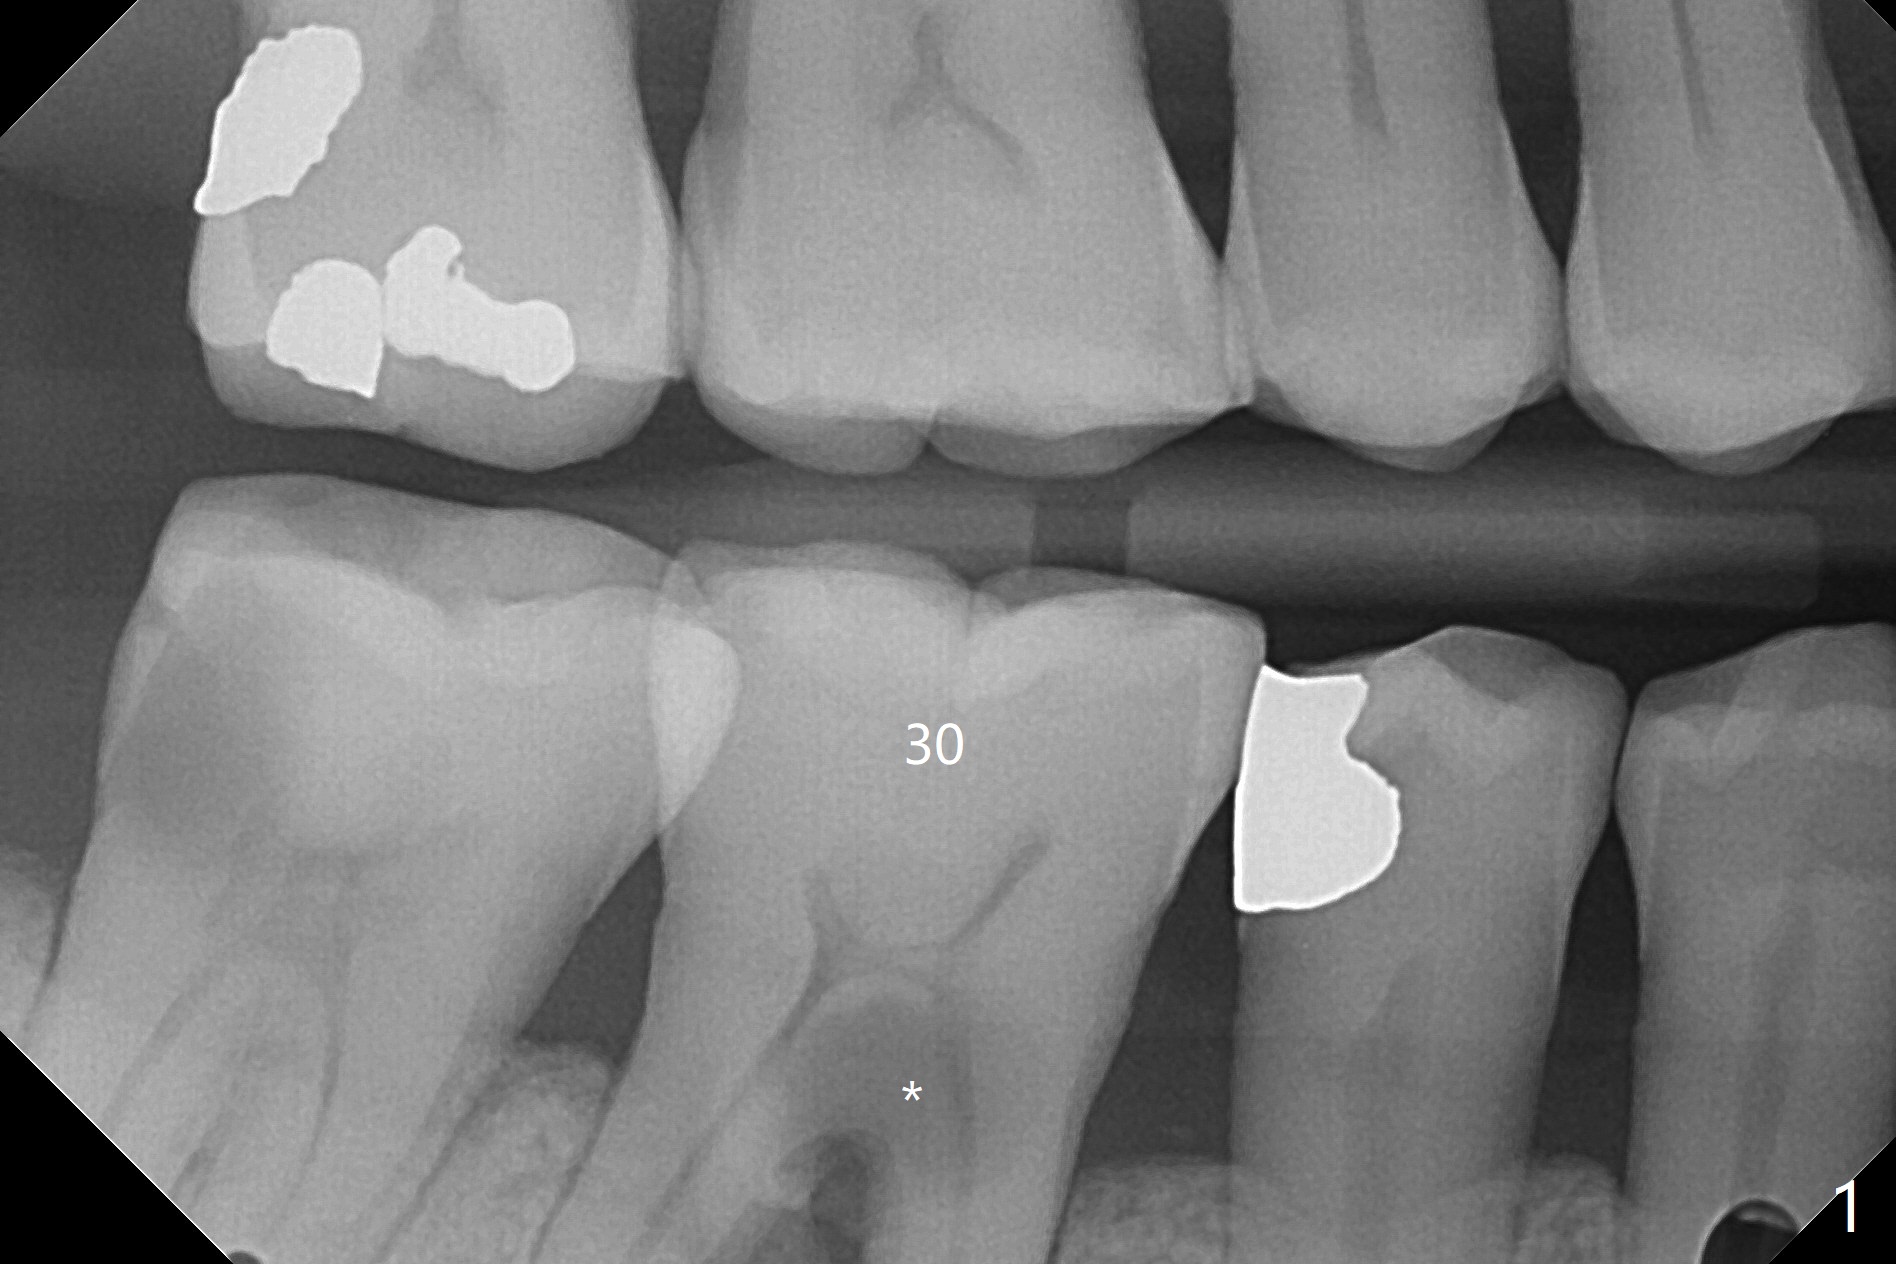

A 65-year-old man has nocturnal pain associated with #30 lingual furca caries and gingival recession (Fig.1,2). PRF (x2) and sticky bone will be used to repair the lingual soft and hard tissue defects. CT shows the submandibular fossa (Fig.3 <), dictating a short implant 10 mm, Fig.4). To place the implant in the septum (Fig.3 S), the coronal portion of the tooth is removed (Fig.5 black area) so that the roots are able to keep the osteotomy without deviation (Fig.6 red arrow). It is possible to place the implant in a trajectory mesiodistally (Fig.7 in fact after root extraction (arrows)). To prevent buccolingual deviation, a small implant (4 mm in diameter) is designed so that it will NOT touch the buccal (B in Fig.8) or lingual (L) plates. The bone density of the cortex and medulla is 2000 and 1400 units, respectively. To reduce the chance of implant fracture because of the narrow diameter in function, an implant with Titanium V will be used.